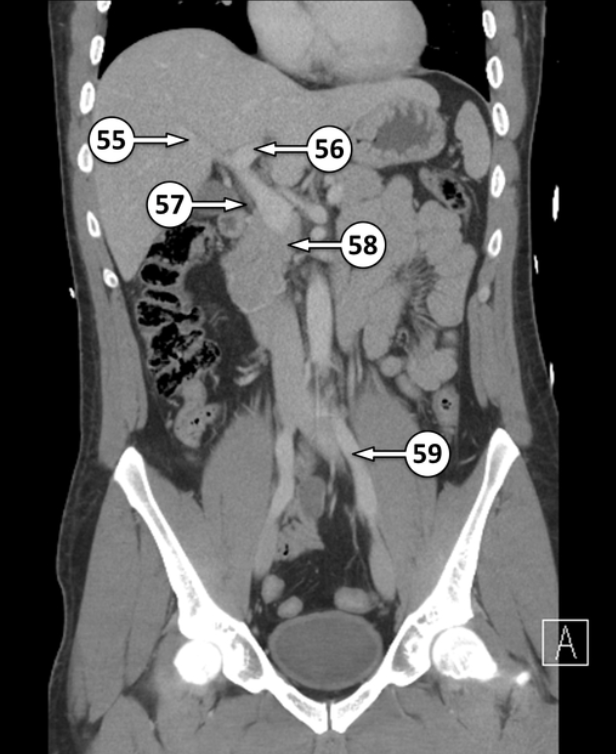

Please label 55 - 58

right portal vein

left portal vein

common bile duct

uncinate process of the pancreas